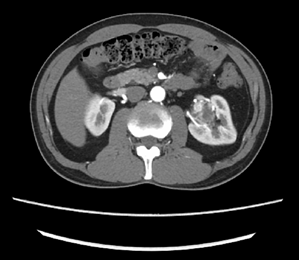

近日,家住金华的胡先生(化名)遇到了重大危机:人到中年,平时身体还算健康,正是事业黄金期,家中的顶梁柱,在一年一度健康体检时,发现左侧肾脏上多了一颗“定时炸弹”。 这枚“炸弹”悄无声息地盘踞在胡先生的左肾上,沉默地挤占、延伸着,竟已超过半个肾脏的大小。这消息对全家来说,不啻惊雷。 当地医院的医生告诉胡先生,这枚肿块的位置较深,手术难度较大,可能无法保留左肾。胡先生怀着沉重的心情和家属讨论后,决定到浙江大学医学院附属第二医院泌尿外科寻求治疗。 (胡先生的左肾肿瘤) 浙大二院泌尿外科的裘益青主任医师接诊了胡先生。面对胡先生的情况,裘医生仔细阅片,告诉胡先生他的年龄不大,肾功能尚可,左肾肿瘤形态和密度考虑恶性肿瘤,而且体积较大,位置较深,位于肾门,需行保肾的肿物切除手术,手术难度较大,建议使用达芬奇机器人辅助手术。 在于家人讨论后,胡先生决定听从裘医生的建议,接受手术治疗。 03一觉醒来剥除“定时炸弹” 术前,裘医生在科室进行了手术讨论,决定了机器人辅助下腹腔镜经后腹腔的手术方式。手术开始,裘医生充分游离左肾周筋膜,开阔视野,暴露肾脏中上极背侧肾门部约4.5cm的那枚“定时炸弹”,它突出肾脏表面,盘踞肾门,血管包绕与周围组织明显粘连,若要完整剥除必定是一场硬战。 裘医生继续沿肾脏表面游离暴露左肾动脉,准备充分后,开始阻断。接下来就是争分夺秒地剥除肿块,因为考虑恶性肿瘤,必然要万分谨慎,不能破坏一点肿瘤的完整性。好在准备充分,视野暴露清晰,裘医生熟练而冷静地剥除肿块,缝合创面。 、 仅仅用时15分钟。阻断的肾动脉再次回复血供,“定时炸弹”已经被“收缴”,术野没有明显出血。 一觉醒来,胡先生肾上的“定时炸弹”已经取下,术后第二天就下床活动,很快就恢复出院了。术后病理报告为肾透明细胞癌。 肾癌是泌尿系统常见的肿瘤,仅次于前列腺癌和膀胱癌,却是泌尿系统致死率最高的恶性肿瘤,其发病率占成人恶性肿瘤的2%~3%。肾癌的治疗和预后与其病理类型和肿瘤分期明显相关,肿瘤发现越早,保留肾脏和功能的机会越大,治疗效果越好。早期肾癌多无临床症状,是通过健康体检或其他检查偶然发现,此类目前约占60%。明显症状出现比如血尿、腰痛、腹部肿块等往往提示晚期肾癌。 所以,早期发现肾癌,主要依靠健康体检,彩色多普勒超声作为初筛检查,超声发现异常时,需要进一步完善增强CT或MRI检查,以帮助医生诊断及对肿瘤进行分期,选择最佳的治疗方式。 专家简介 裘益青 泌尿外科主任医师 熟练掌握腹腔镜下(含机器人辅助)根治性膀胱切除术、保留性神经的根治性前列腺切除术、保留肾单位肾癌手术等。

02 肿瘤体积大 位置深 达芬奇机器人登场